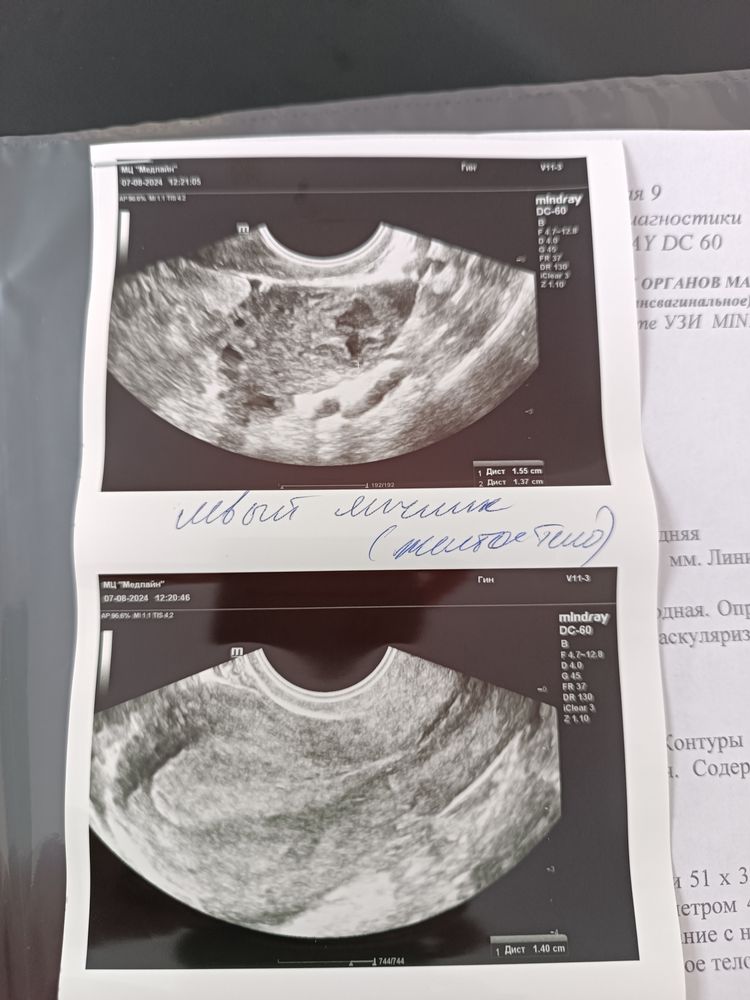

Изображение вот прикрепляю результаты УЗИ может кто-то тоже будет интересоваться Изображение

Юля, У меня после внематочной беременности такой страх что я по поводу и без повода УЗИ делаю. И только после УЗИ уже магу расслабиться. Но и то когда сказали что яйцеклетка ещё могла в матку не опуститься теперь надо молиться чтобы она прошла этот путь в матку благополучно